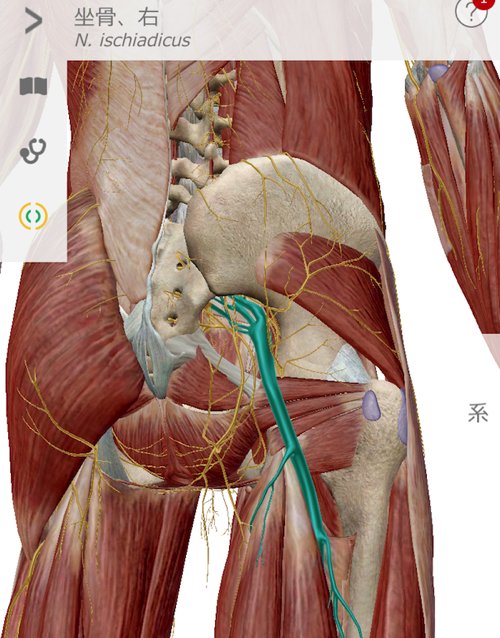

そして腰の痛み。

脊柱管狭窄の部分を触っても軽く叩いても痛みが無いので

脊柱管狭窄と腰の痛みは直接の関係が無いという前提で

仙骨から鼠径部までの施術を丁寧に行いました。

整形外科で治らなかった脊柱管狭窄症の原因

痛みの原因はズバリ膝のヨジレ。

膝から鼠径部にかけての硬直と

太腿から臀部にかけての硬直が腰骨を引っ張ってしまい

骨盤を正しい位置からずらしてしまい

ズレた骨盤が神経に触れて痛かったのです。

腰の痛みは結果であって原因ではありません。

だから腰をいくら治しても治らないのです。